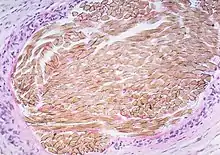

| Picture of a granuloma (without necrosis) as seen through a microscope on a glass slide: The tissue on the slide is stained with two standard dyes (hematoxylin: blue, eosin: pink) to make it visible. The granuloma in this picture was found in a lymph node of a patient with a Mycobacterium avium infection. | |

Histiocytes (specifically macrophages) are the cells that define a granuloma. They often fuse to form multinucleated giant cells (Langhans giant cell).[7] The macrophages in granulomas are often referred to as "epithelioid". This term refers to the vague resemblance of these macrophages to epithelial cells. Epithelioid macrophages differ from ordinary macrophages in that they have elongated nuclei that often resemble the sole of a slipper or shoe. They also have larger nuclei than ordinary macrophages, and their cytoplasm is typically pinker when stained with eosin. These changes are thought to be a consequence of "activation" of the macrophage by the offending antigen.

The other key term in the above definition is the word "organized" which refers to a tight, ball-like formation. The macrophages in these formations are typically so tightly clustered that the borders of individual cells are difficult to appreciate. Loosely dispersed macrophages are not considered to be granulomas.